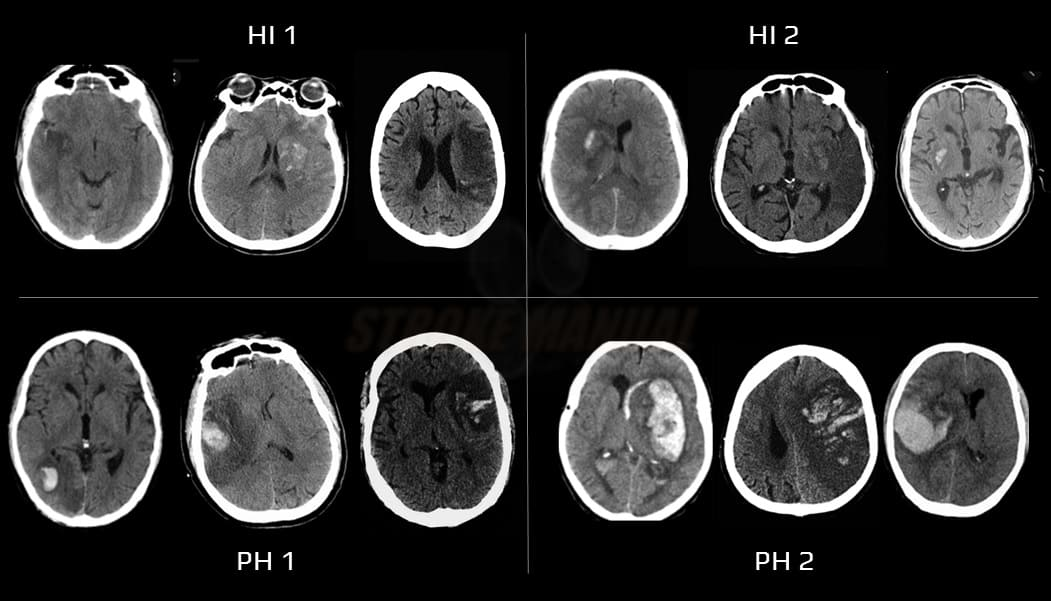

• 1a : HI1 : pétéchies isolées au sein du tissu infarci, sans effet de masse ;

• 1b : HI2 : pétéchies confluentes au sein du tissu infarci, sans effet de masse ;

• 1c : PH1 : hématome occupant ≤ 30% de la zone infarcie, sans effet de masse significatif ;

• PH2 : hématome occupant > 30% de la zone infarcie, avec un effet de masse évident attribuable à l'hématome ;

• Infarctus hémorragique de type 1 (HI1) : pétéchies isolées au sein du tissu infarci, sans effet de masse.

• Infarctus hémorragique de type 2 (HI2) : pétéchies confluentes au sein du tissu infarci, sans effet de masse attribuable au saignement.

• Hématome parenchymateux type 1 (PH1) : lésion homogène occupant ≤ 30% de la zone infarcie, avec un effet de masse minime attribuable à l'hématome.

• Hématome parenchymateux type 2 (PH2) : lésion homogène occupant > 30% de la zone infarcie, avec un effet de masse substantiel attribuable à l'hématome.